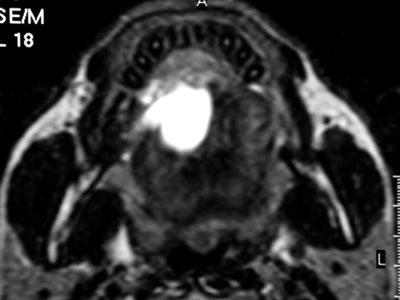

CT and MR are currently the primary imaging modalities to assess the oral cavity. CT is preferred in patients presenting with infectious/inflammatory syndrome. According to Borges, in patients presenting with oral cavity cancer, the use of dental CT software with the acquisition of para-axial and parasagittal high-resolution images in bone algorithm is most valuable in depicting early cortical bone erosion. MRI provides better soft-tissue resolution, and is the first choice in evaluating the deep extent of tumors and for the management of patients presenting with submucosal lesions.

Axial T2-weighted MR image through the floor of the mouth shows a small squamous cell carcinoma (SCC) strategically located in the anterior floor of the mouth. The SCC is obstructing the draining ducts of the sublingual gland with an associated plunging ranula. Image courtesy of Dr. Alexandra Borges.Referring to the choice of imaging technique, she highlights the importance of considering different patients' specificities. Heavy smokers and drinkers prone to salivary stasis, difficulty in swallowing, and dyspnea are not good candidates for MRI, as this technique is very prone to motion artifacts, and patients with many dental fillings and/or dental implants may do better with MRI than with CT, she explained.